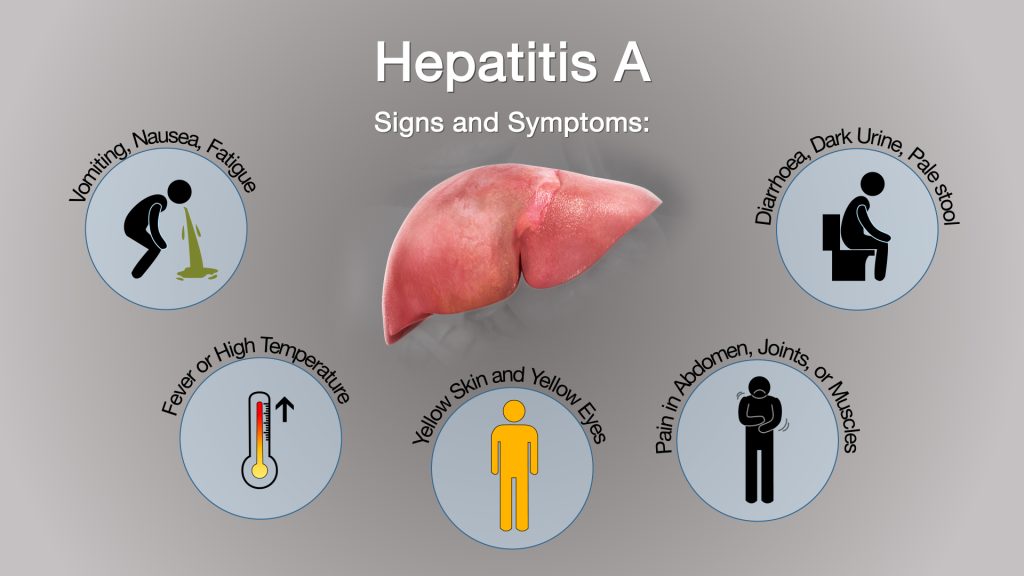

Hepatitis treatment

"Hepatitis treatment depends on the specific type of hepatitis and its stage. Antiviral medications are commonly used for hepatitis B and C, aiming to suppress viral replication and reduce liver inflammation. Lifestyle modifications, including a healthy diet and avoiding alcohol, are essential for supporting the liver's recovery. Regular monitoring of liver function and, in some cases, liver transplantation for severe liver damage, are part of a comprehensive treatment approach. Consult with a healthcare professional for personalized hepatitis treatment plans tailored to your specific condition. #HepatitisTreatment #LiverHealth"

Viral Hepatitis Prevention

"Preventing viral hepatitis is achievable through vaccination, emphasizing the importance of Hepatitis A and B vaccines. Promote consistent handwashing and safe water, reducing the risk of hepatitis A and E transmission. Advocate for safe injection practices to prevent hepatitis B and C, and stress the importance of safe sex with barrier methods. Education and awareness campaigns empower communities to recognize risks and adopt preventive measures. Regular screening, especially for high-risk groups, ensures early detection and intervention, a key strategy in the fight against viral hepatitis.